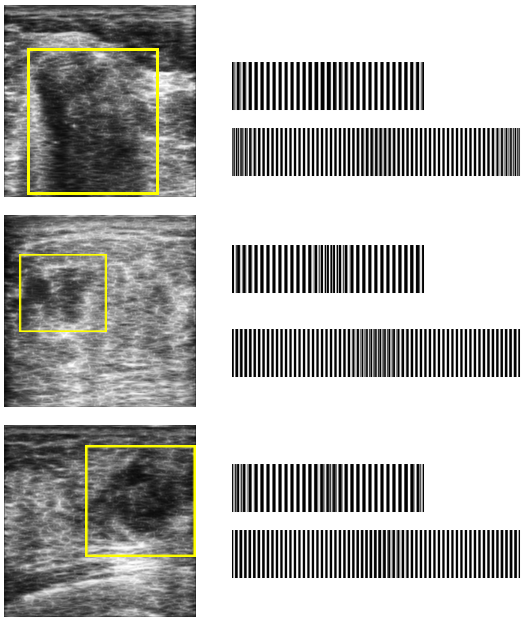

It has recently been proposed to threshold all projections for individual angles based on a “local” threshold for that angle to create a barcode of all thresholded projections [15]: “A simple way for thresholding the projections is to calculate a typical value via median operator applied on all non-zero values of each projection”. Fig. 1 illustrates how Radon barcodes (RBCs) are generated.

In [15], only “global” barcodes were used, meaning that one barcode was extracted for the entire image. But it was recognized that using “local” barcodes may be of more significance when dealing with specific regions of interest (ROIs) (see Fig. 2). In this research, the two were combined and every image was tagged with two barcodes. The “global” barcode captures the general appearance of the image, and the “local” (or ROI-based) barcode captures the texture and intensity variations of the tumour.